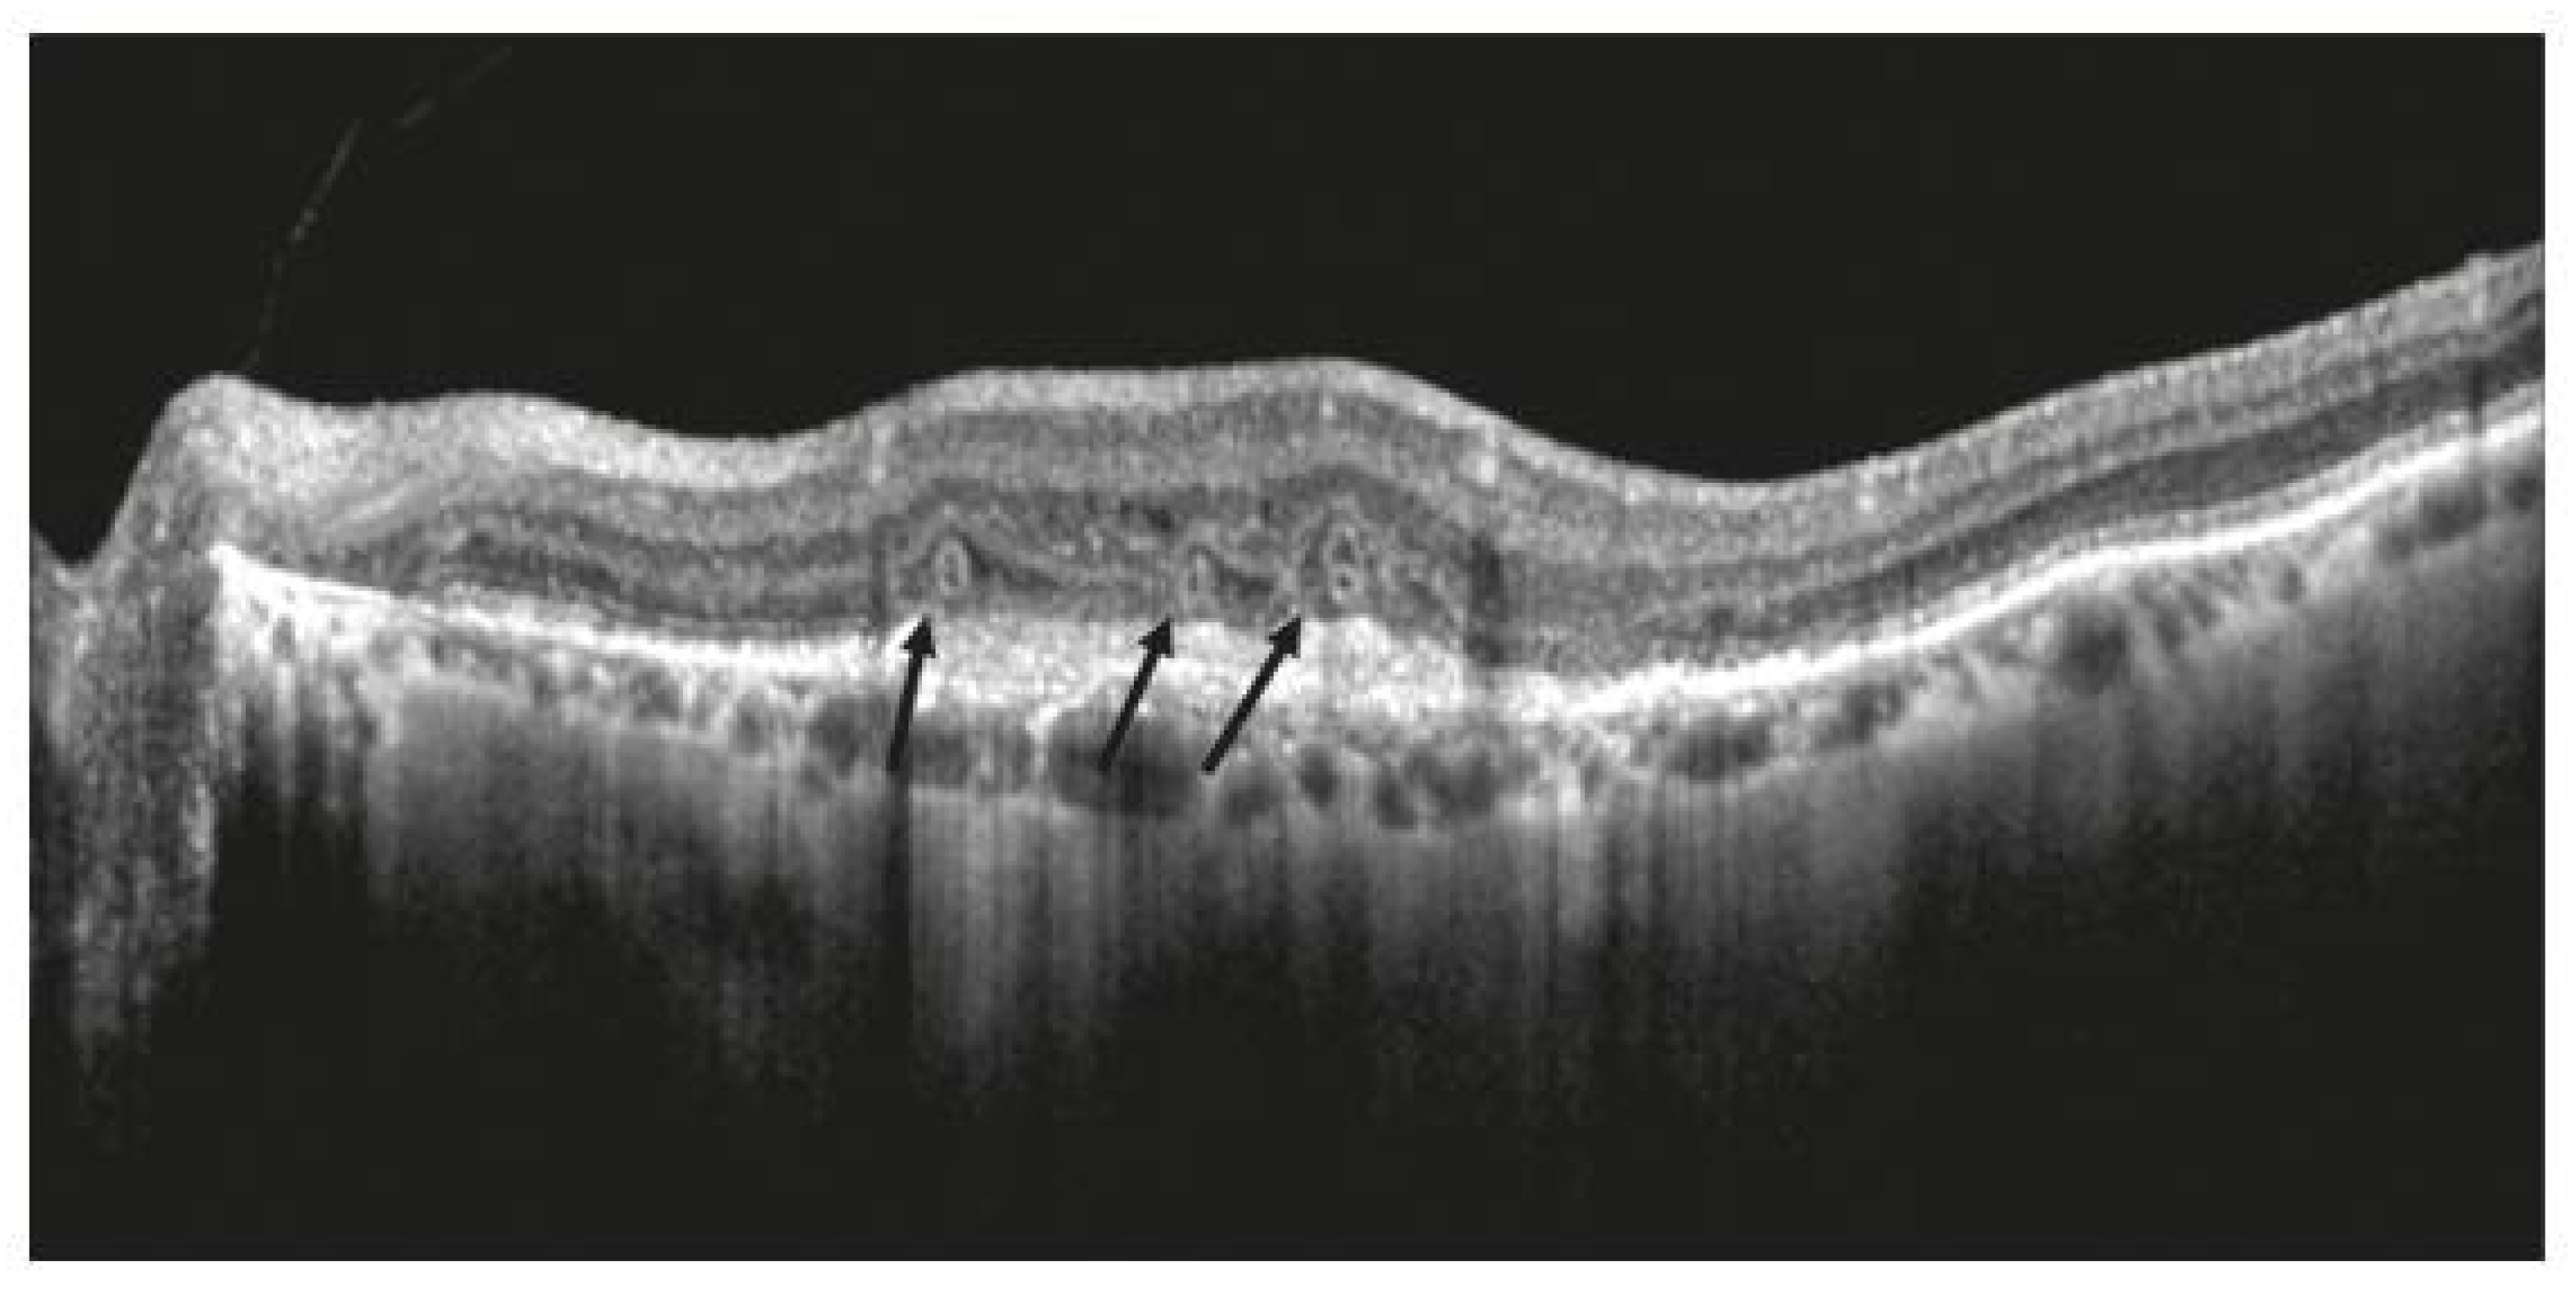

3.3. Outer-Retinal Damage

- Zweifel, S.A.; Engelbert, M.; Laud, K.; Margolis, R.; Spaide, R.F.; Freund, K.B. Outer retinal tubulation: A novel optical coherence tomography finding. Arch. Ophthalmol. 2009, 127, 1596–1602, Erratum in Arch Ophthalmol. 2012, 130, 856. [Google Scholar] [CrossRef]

- Ooto, S.; Vongkulsiri, S.; Sato, T.; Suzuki, M.; Curcio, C.A.; Spaide, R.F. Outer Retinal Corrugations in Age-Related Macular Degeneration. JAMA Ophthalmol. 2014, 132, 806–813. [Google Scholar] [CrossRef]